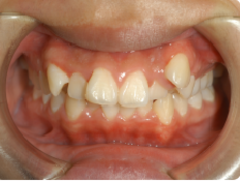

「上の前歯のデコボコを治したい」このような相談は、非常に多いです。

マウスピースで簡単に治せます。他院だと相場で1個につき20,000円前後。

当院は1個につき5,000円です。